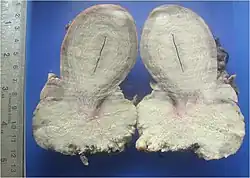

Plattenepithelkarzinome wachsen warzenartig (verrukös) oder ulzerierend und ahmen das verhornende oder nicht-verhornende Plattenepithel in unterschiedlichem Umfang nach. Typisch für sie ist ein Zytoskelett aus Zytokeratin (CK). Hochdifferenzierte Karzinome dieser Entität verhornen und bilden, da die Hornschuppen im Tumorinneren liegen und nicht abgeschilfert werden können, zwiebelschalenartig geschichtete Hornkugeln (Hornperlen), die mikroskopisch meist eindeutig diagnostizierbar sind. Gering differenzierte Karzinome verlieren die Fähigkeit zur Hornbildung. Sie bilden sehr polymorphe (vielformige), solide Tumoren. Sehr stark entdifferenzierte (anaplastische) Plattenepithelkarzinome können in der spindelzelligen (fusiformen) Variante wie Sarkome aussehen.

Als invasiv und damit metastasierungsfähig gelten Plattenepithelkarzinome, wenn sie die Basalmembran durchbrochen haben. Meist lässt sich dann auch eine desmoplastische Stromareaktion (reaktives Bindegewebe) nachweisen. Weitere Zeichen der Invasion sind Einbrüche in Blut- und Lymphgefäße, Perineuralscheideninvasion, destruierendes Wachstum und Metastasen.

Nicht-Invasive Krebsvorstufen werden als Plattenepitheldysplasie, intraepitheliale Neoplasie (IEN) oder squamöse intraepitheliale Läsion (SIL) bezeichnet und in Schweregrade eingeteilt. Carcinoma in situ (Cis) ist gleichbedeutend mit schwerer Dysplasie bzw. high grade IEN / SIL. Leichtgradige Dysplasien können sich spontan zurückbilden, bei schweren Dysplasien ist der Übergang in ein invasives Karzinom jederzeit möglich.